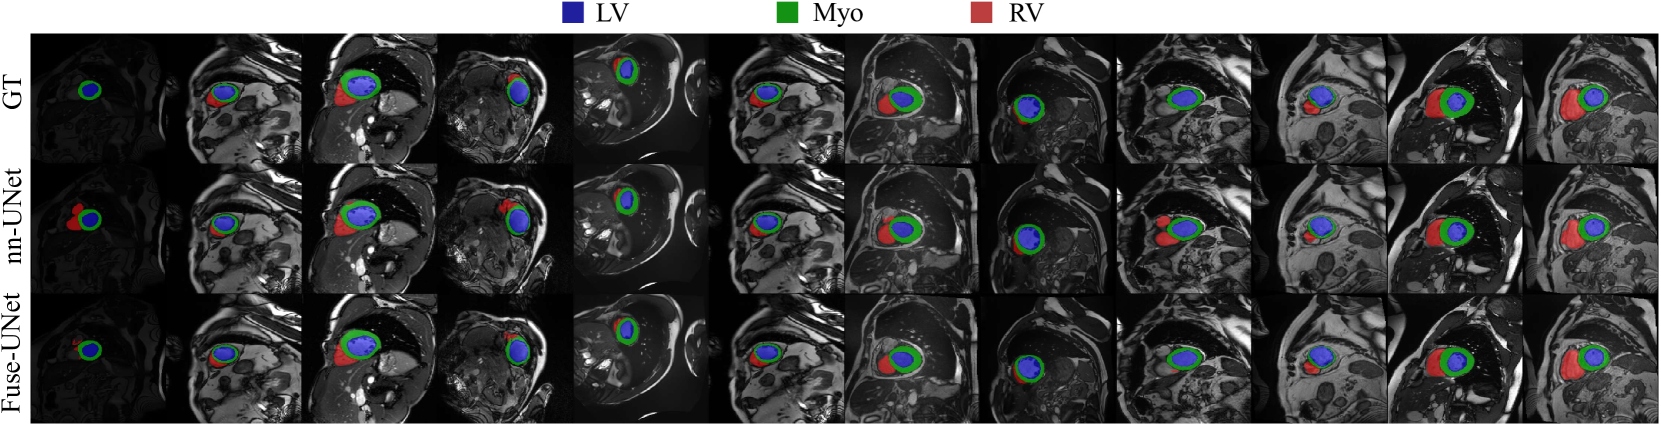

Refer to caption

(a) Visualization on the ACDC

Fig. 3 illustrates the visual segmentation results of FuseUNet, where (a), (b), and (c) correspond to the ACDC, KiTS, and MSD brain tumor datasets, respectively. In Figure 3 (a), nn-UNet frequently makes errors in identifying the right ventricle (RV), sometimes misclassifying unrelated tissues as the RV or missing portions of it entirely. FuseUNet significantly mitigates these issues. Fig. 3(b) shows that nn-UNet occasionally fails to fully recognize the kidneys and often confuses kidney tumors with cysts. This is particularly evident in the third row, where nn-UNet incorrectly classifies most cysts as tumors, even in the absence of tumor tissue. FuseUNet greatly improves upon this. In Fig. 3(c), UNETR exhibits challenges such as incomplete tumor recognition and missing enhanced tumor regions, both of which are notably addressed by FuseUNet.